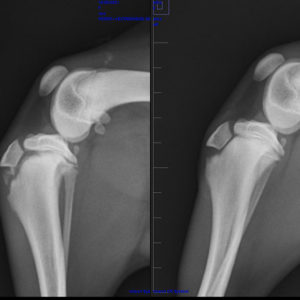

A ZAMBRA la recogimos del CPA con una avulsión de tuberosidad tibial en la pata derecha trasera. Ya esta operada y recuperándose perfectamente, aunque cuesta que haga reposo porque todo lo que quiere es jugar y pasarlo bien. Una perrita de personalidad abierta. Cariñosa y muy agradecida. Sumisa con las personas.